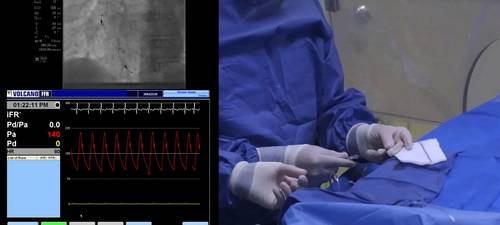

Shaping the straight-tipped Verrata wire prior to insertion

Dr Davies illustrates the shaping of the straight-tipped Verrata wire prior to insertion. A gentle "J-shape" curve is shaped at the tip of the wire, so the shape resembles a standard angioplasty guidewire